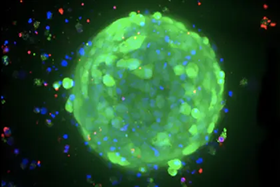

Breast cancer organoids

Image Credit: Molecular Devices UK Ltd

Clinically relevant tumor models are used to better understand the mechanism, examine tumor biomarkers, and test anticancer medicines.

Breast cancer organoids

Image Credit: Molecular Devices UK Ltd

Breast cancer patients’ survival rates depend heavily on early identification and treatment. This involves the use of therapeutically relevant tumor models to better understand the mechanism, identify tumor biomarkers, and screen anticancer medicines. Breast cancer tumoroids provide a platform for investigating tumor physiology and response to targeted therapy.